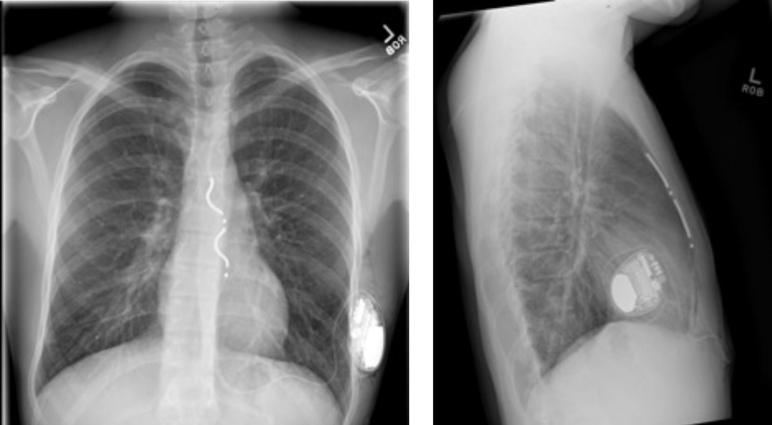

We present a case of long QT syndrome type 2 in a competitive runner who underwent implantation of a primary prevention extravascular implantable cardioverter defibrillator with a rapid return to partial activity within 2 weeks and a return to full activity within 4 weeks of implantation without affecting wound healing or device function.

我们报告一例2型长QT综合征的竞技跑步者病例,该患者接受了一级预防的血管外植入式心脏复律除颤器植入术,术后2周内迅速恢复部分活动,植入后4周内恢复完全活动,且未影响伤口愈合或设备功能。